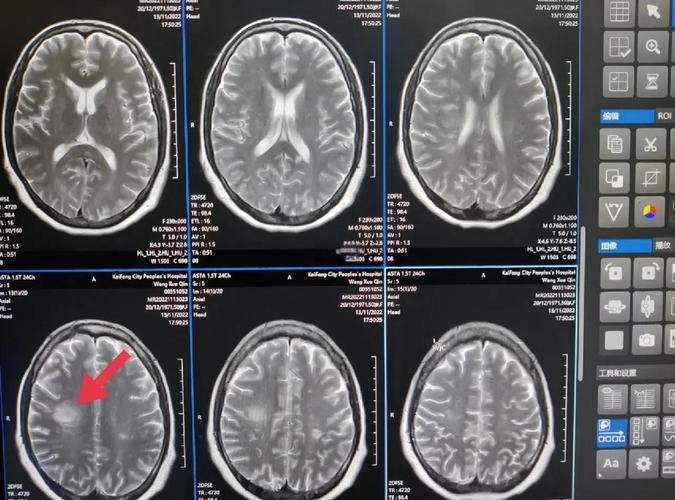

| MRI (DWI序列) | 看脑组织 | 可以(发病数分钟至1小时内) | 金标准:对早期、超早期的脑梗塞病灶检出率极高,是诊断急性脑梗最敏感的检查。 |